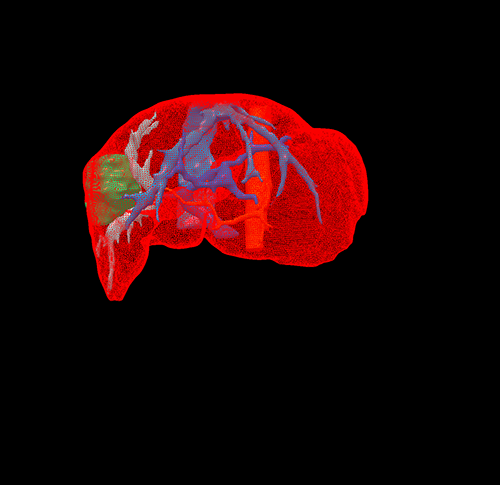

右肝癌复发-门静脉栓塞+肿瘤动脉栓塞后右半肝切除